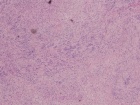

50 year old male with a several year history of right ankle mass, which the patient states has gotten larger in the past few months. On PE he has a tender, egg shaped mass in the distal posterior aspect of his left calf.

Zoom image: Cell stain Cell stain.